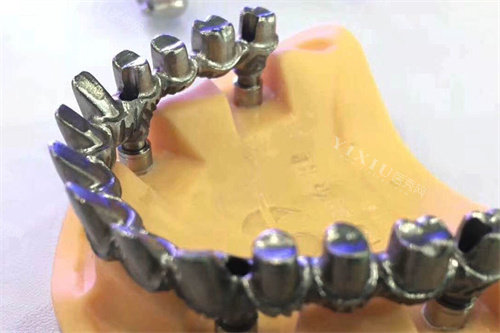

金属合金材质

金属合金材质主要分为贵金属和非贵金属两大类。贵金属包括金、白金等,非贵金属则以钴铬合金为代表。这类材质的比较大的优势在于其出色的强度和耐用性,特别适合用于后牙区的修复。金属合金能够承受较大的咬合力,使用寿命较长。然而,金属材质在美观性方面存在明显不足,其颜色与天然牙齿差异较大,可能影响笑容的自然度。此外,部分患者可能对某些金属成分过敏,在选择时需要特别注意这一点。